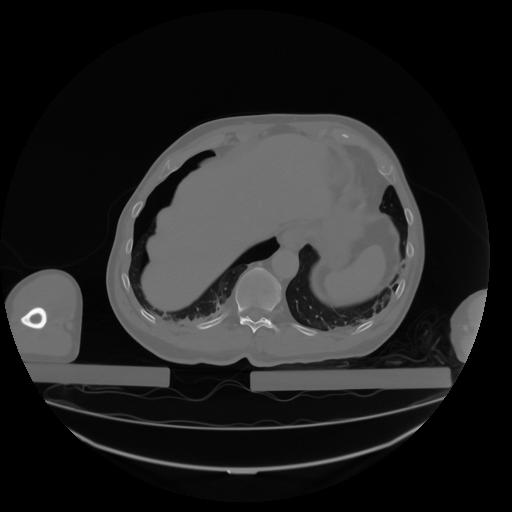

27 CUERPO,CE,Axial,3.0,CUERPO,,